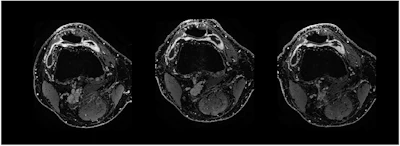

Contrast-enhanced T1 weSPGR images of the knee of a patient from the GAE group at the level of the suprapatellar recess. The baseline image (left) shows a marked synovial enhancement. There was no change one month after treatment (middle image) and four months after treatment (right image).European Radiology

The finding is from a comparison among 58 participants with mild to moderate knee osteoarthritis who were unresponsive to conservative treatment, and further found no MRI differences between the groups in synovitis reduction, noted lead author Tijmen van Zadelhoff, MD, of Erasmus MC in Rotterdam, the Netherlands, and colleagues.